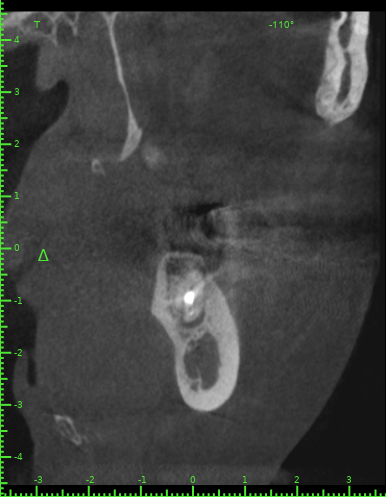

Katya88 Опубликовано 28 июля, 2021 Поделиться Опубликовано 28 июля, 2021 Мой стоматолог терапевт советует удалить, так как там кисты, а ортопед советует найти того, кто займется лечением. КТ прилагаю https://drive.google.com/file/d/1Z-neEH63BszTXxa8bAOG1tgsrIrsqrVK/view?usp=drive_web Ссылка на комментарий

Женька Опубликовано 28 июля, 2021 Поделиться Опубликовано 28 июля, 2021 2.6 2.7 3.7 На 3.5 и 1.5 стоит обратить внимание 1.5 1 Ссылка на комментарий

Женька Опубликовано 28 июля, 2021 Поделиться Опубликовано 28 июля, 2021 54 минуты назад, Katya88 сказал: 1.5 менять коронку как минимум снять существующую конструкцию и посмотреть клинически на зуб(ы). 1.5 на КТ выглядит удручающе. По остальным, я бы поддержал ортопеда и попытался зубы сохранить. Пусть коллеги меня поправят. 1 1 Ссылка на комментарий